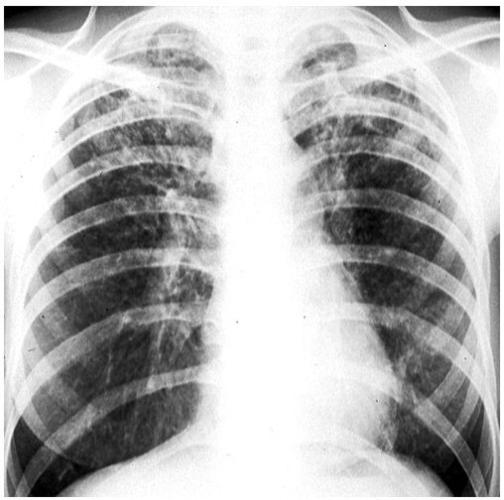

肺部感染胸片,肺部感染片子

5种肺部感染的影像学鉴别(多图)

胸片显示特征性的双肺上叶纤维化.

基本介绍 x线胸片的特点x线胸片能清晰地记录肺部的胸片大体病变,如